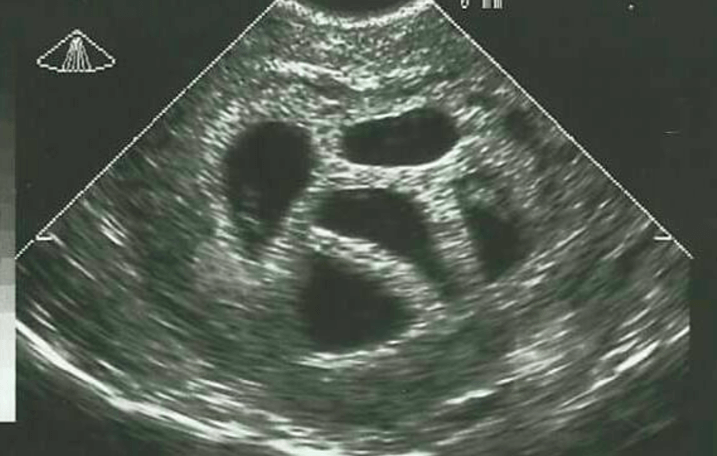

Es gibt etwas Besonderes über eine Mutter namens Susan zu erzählen, die vor zwanzig Jahren vor einer schwierigen Entscheidung stand. Im Alter von 28 Jahren erfuhr sie, dass sie mit Fünflingen schwanger war. Die Ärzte, die sie begleiteten, rieten ihr zu einem „selektiven Schwangerschaftsabbruch“. Dies bedeutet, dass man ein oder mehrere Embryonen oder Föten entfernen lassen kann, um die Überlebenschancen der anderen zu verbessern. Aber Susan hielt dies für keine Option und ignorierte den Rat.